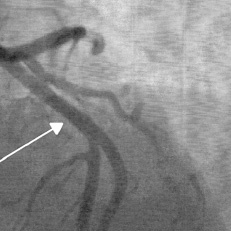

Abb. 2

nach Stent-Implantation

Der Befund von Herrn Peter bietet sich für eine Behandlung mit der neuen Gefässstütze an. Der Stent ist auf einem Ballon am Ende eines dünnen, flexiblen Katheters montiert und wird nun im Koronargefäss platziert. Durch Aufblasen des Ballons dehnt sich «Absorb» auf und presst die arteriosklerotischen Ablagerungen an die Gefässwand. Ballon und Katheter werden zurückgezogen, «Absorb» verbleibt im Gefäss. Der Blutfluss ist wiederhergestellt. In circa zwei Jahren wird sich der Stent vollständig aufgelöst haben (Abb. 2).